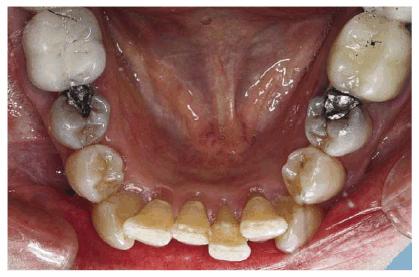

Figure 29-1M: The maxillary arch shows anterior crowding and defective amalgam restorations.

Figure 29-1N: Following 12 months of orthodontic treatment, the patient's amalgam restorations were replaced with posterior composite resin.

Figure 29-1O: Interdisciplinary 949o141j therapy including orthodontics, periodontics, and restorative dentistry combined to produce this attractive result 2 years following the initiation of treatment in this now younger-looking 78-year-old lady.